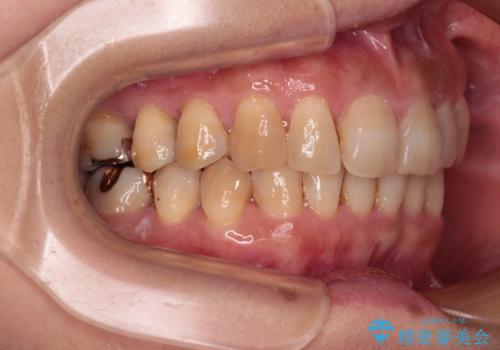

ディープバイトと前歯のデコボコ インビザラインによる矯正治療

- 前歯のディープバイトと叢生を気にして来院された患者様です。

目立ちにくい装置を希望されていたため、ワイヤー装置とインビザラインを提案したところ、インビザラインを希望されました。

下顎大臼歯が手前に倒れていたため、起き上がらせることで咬み合わせ高さを挙上し、ディープバイトと叢生を改善することとしました。

インビザライン特有の奥歯の噛みにくさが治療後半に発言しましたが、無事に終了させることができました。